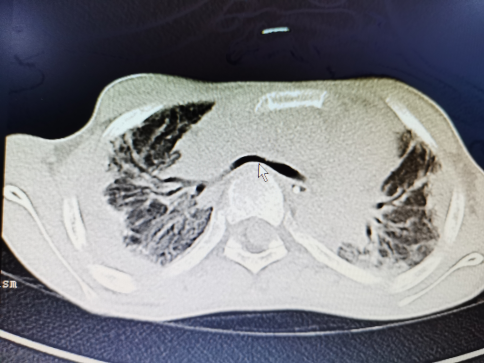

“孩子的脊柱向前擠壓,脊柱和胸骨間距不到2CM,胸廓壓迫肺、氣道、心臟大血管,加上右鎖骨下動脈畸形繞到了氣管前面,雙向的壓迫促使氣管被壓得唯獨(dú)一條縫,假設(shè)不手術(shù)治愈,會有生命風(fēng)險?!睔舛葍?nèi)科副主任醫(yī)生張志功表達(dá)。通過兒科、氣度內(nèi)科、麻醉科、小兒骨科、放射科、呼吸外科多科協(xié)作,氣度內(nèi)科周文武主任醫(yī)生、張志功副主任醫(yī)生通過3D打印模型頻頻模仿手術(shù),終極為陽陽施行了胸廓成型及胸大肌肌瓣成形+支氣管纖支鏡檢驗(yàn),開胸置入鈦板將孩子的胸廓形式重塑,并將迷走動脈離斷后從新吻合,再進(jìn)行了氣管懸吊,壓迫陽陽氣管的原因十足解除,術(shù)后陽陽經(jīng)過修復(fù)治愈終究擺脫了呼吸機(jī),正進(jìn)行呼吸痊愈。